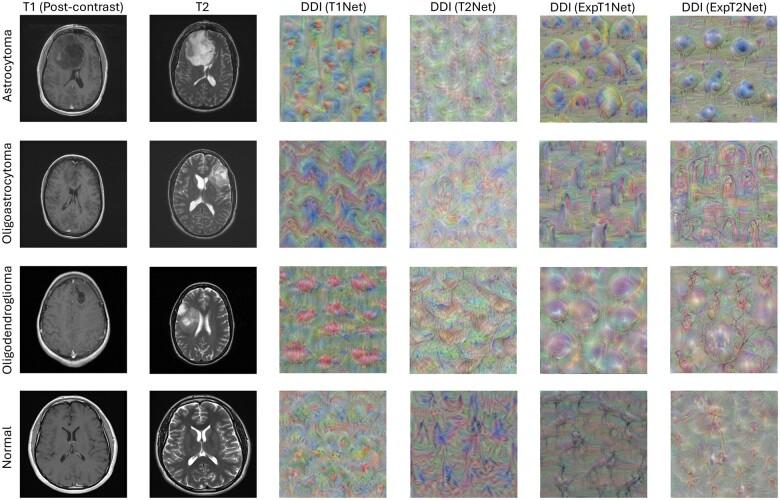

Convolutional neural networks (CNNs) are powerful tools that can be trained on image classification tasks and share many structural and functional similarities with biological visual systems and mechanisms of learning. In addition to serving as a model of biological systems, CNNs possess the convenient feature of transfer learning where a network trained on one task may be repurposed for training on another, potentially unrelated, task. In this retrospective study of public domain MRI data, we investigate the ability of neural network models to be trained on brain cancer imaging data while introducing a unique camouflage animal detection transfer learning step as a means of enhancing the networks' tumor detection ability. Training on glioma and normal brain MRI data, post-contrast T1-weighted and T2-weighted, we demonstrate the potential success of this training strategy for improving neural network classification accuracy. Qualitative metrics such as feature space and DeepDreamImage analysis of the internal states of trained models were also employed, which showed improved generalization ability by the models following camouflage animal transfer learning. Image saliency maps further this investigation by allowing us to visualize the most important image regions from a network's perspective while learning. Such methods demonstrate that the networks not only 'look' at the tumor itself when deciding, but also at the impact on the surrounding tissue in terms of compressions and midline shifts. These results suggest an approach to brain tumor MRIs that is comparable to that of trained radiologists while also exhibiting a high sensitivity to subtle structural changes resulting from the presence of a tumor.

卷积神经网络(CNNs)是强大的工具,可用于图像分类任务的训练,并且在结构和功能上与生物视觉系统及学习机制有许多相似之处。除了作为生物系统的模型外,卷积神经网络还具有迁移学习的便利特性,即在一项任务上训练的网络可重新用于另一项可能不相关的任务的训练。在这项对公共领域MRI数据的回顾性研究中,我们研究了神经网络模型在脑癌成像数据上进行训练的能力,同时引入了一个独特的伪装动物检测迁移学习步骤,以此作为增强网络肿瘤检测能力的一种手段。我们在胶质瘤和正常脑MRI数据(增强后T1加权和T2加权)上进行训练,证明了这种训练策略在提高神经网络分类准确率方面的潜在成功。我们还采用了定性指标,如对训练模型内部状态的特征空间和深度梦境图像分析,结果表明模型在伪装动物迁移学习后具有更好的泛化能力。图像显著性图通过让我们在学习过程中从网络的角度可视化最重要的图像区域,进一步推动了这项研究。这些方法表明,网络在做出决策时不仅“查看”肿瘤本身,还会考虑肿瘤对周围组织在压迫和中线移位方面的影响。这些结果表明了一种针对脑肿瘤MRI的方法,该方法与训练有素的放射科医生的方法相当,同时对肿瘤存在导致的细微结构变化也具有高敏感性。